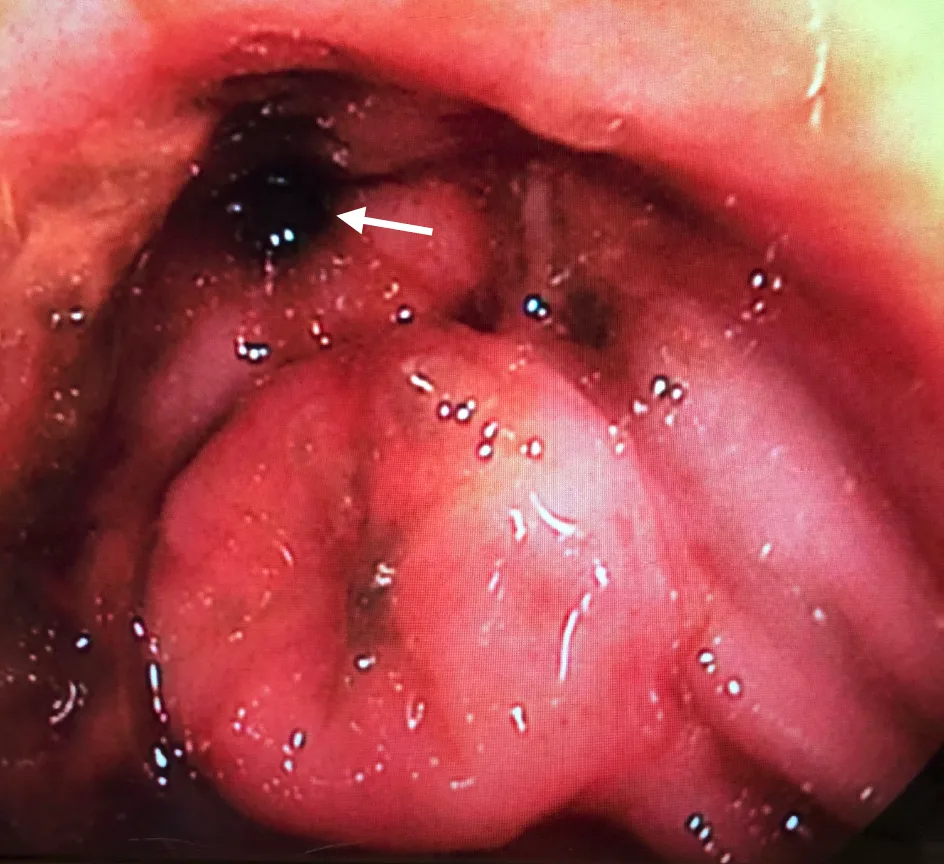

Radiography is nonspecific, and radiographs may appear normal. Ultrasonographic findings may include thickening of the general bowel wall or muscularis layer (Figure 1), mucosal changes, and mesenteric lymphadenopathy; however, ultrasonography is not sensitive or specific for IBD, and results may be normal.19,20

Ultrasound of the duodenum in a cat showing mild generalized muscularis layer thickening (arrow). The corrugated appearance and increased gas within the lumen (dashed arrow) support spastic hypermotility consistent with duodenitis, assuming an upper GI linear foreign body has been excluded.